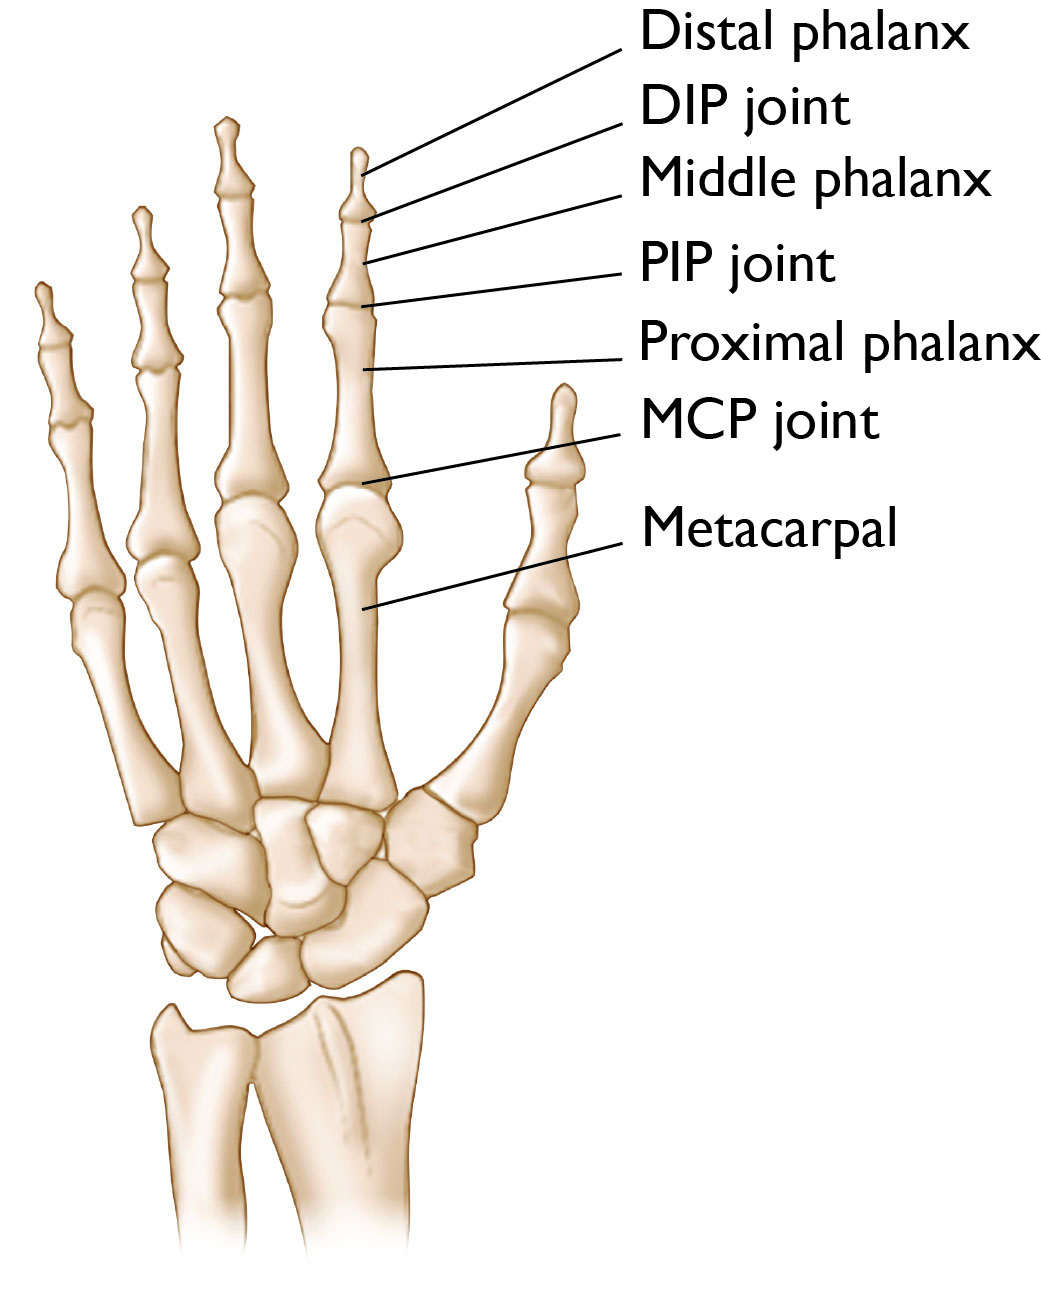

Each finger (not the thumb) has three bones connected by joints.

• The distal phalanx is the last bone of the finger at the very tip. It connects to the middle phalanx, the middle bone of the finger, via the DIP joint.

• The middle phalanx connects to the proximal phalanx, the bone in the finger closest to the hand, via the PIP joint.

• The proximal phalanx connects the finger bone to the hand bone (metacarpal) via the MCP joint.

Most implants are designed to replace the PIP joints or the MCP joints, where motion is most important for finger function. Patients with severe DIP joint issues typically are treated with fusion (also called arthrodesis) instead of replacement.

Illustration Showing the Bones and Joints of the Fingers

Illustration showing the three finger bones (distal phalanx, middle phalanx, and proximal phalanx) and the joints that connect them to each other (DIP and PIP joints) and to the metacarpal bones in the hand (MCP joint).